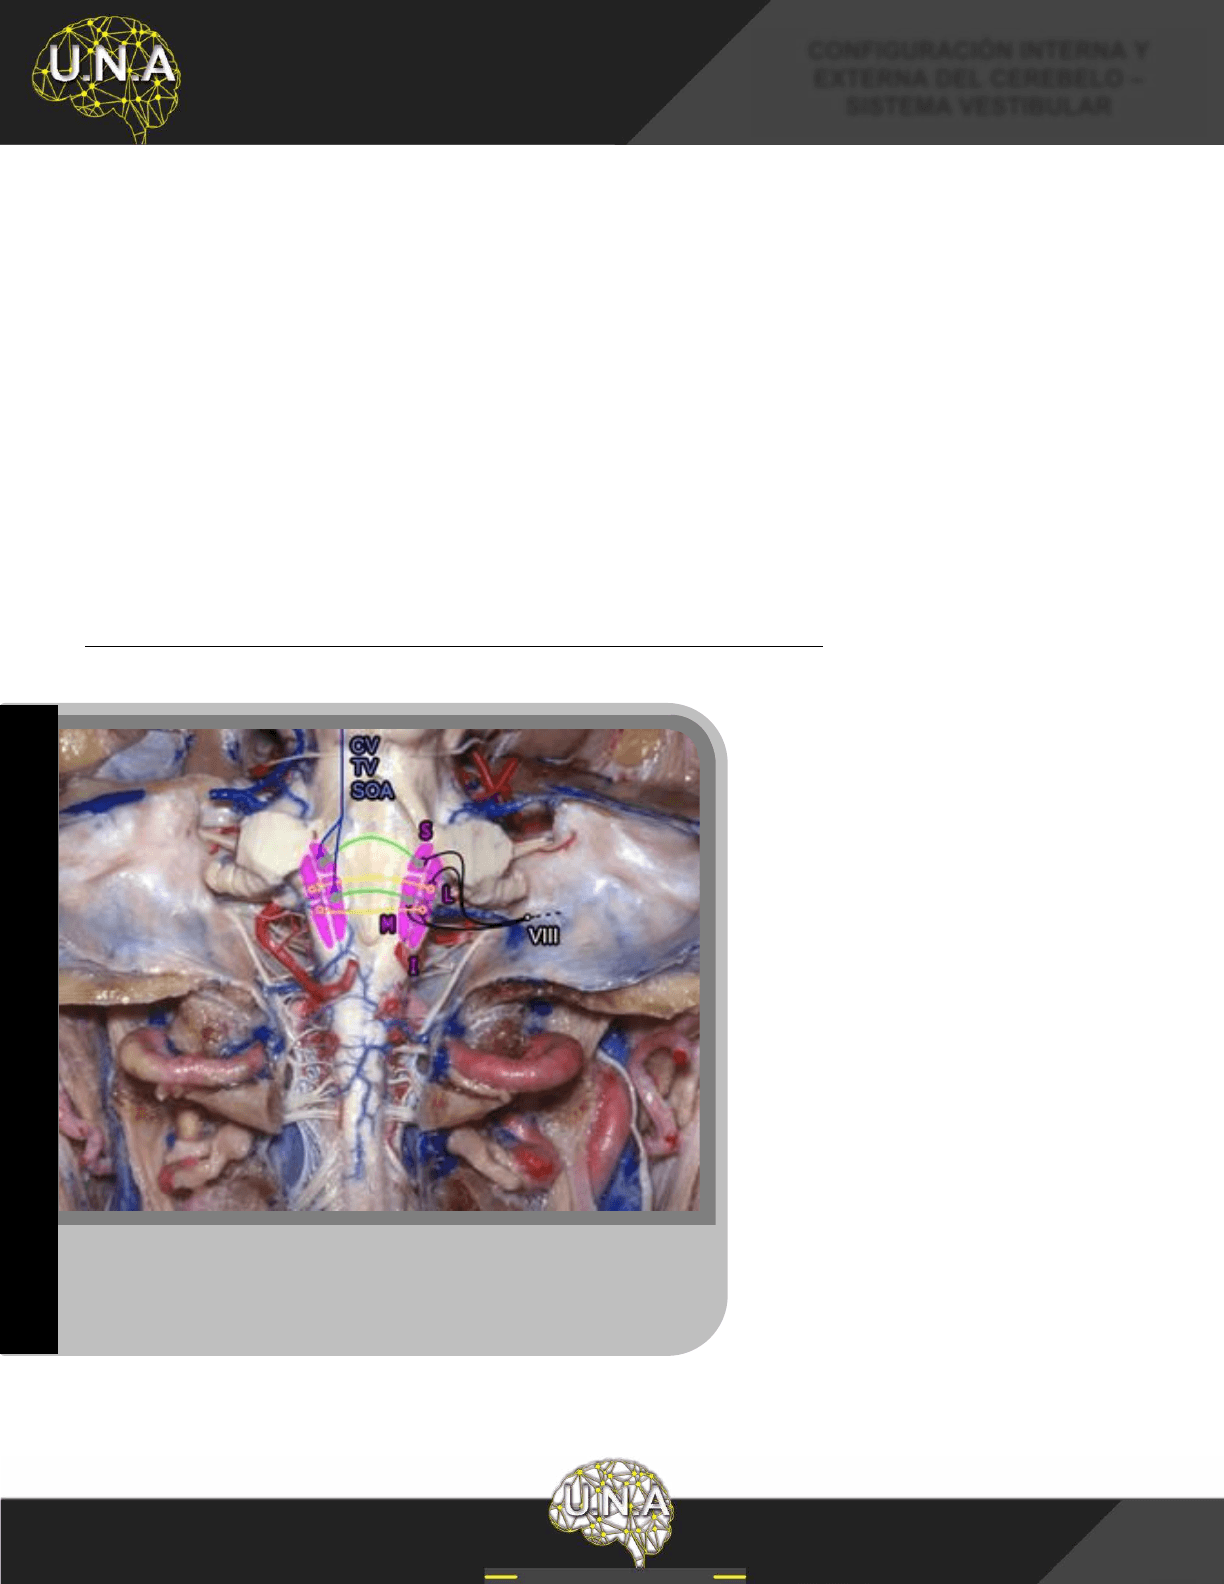

CUARTO VENTRÍCULO (IV)

El IV ventrículo se localiza entre el tronco del encéfalo y el cerebelo. Presenta una pared rostral (piso),

una pared dorsal (techo), 4 bordes y 4 ángulos, confiriéndole una forma romboidal. Los velos medulares

superior e inferior conforman su techo y la cara dorsal del tronco encefálico su piso.

Recibe el LCE desde su plexo coroideo y desde el III ventrículo a través del acueducto cerebral,

derivando este hacia el espacio subaracnoideo a través de los forámenes laterales [Lushka] y medial

[Magendie].

PISO DEL CUARTO VENTRÍCULO

El piso del cuarto ventrículo, también llamado fosa romboidea, corresponde a la cara dorsal del puente y la

médula oblongada, para describirlo se lo divide en dos triángulos uno superior y otro inferior, opuestos por

sus bases, separados por las estrías medulares (fibras blancas que emergen de la línea media y se dirigen

hacia los tubérculos acústicos).

Vista dorsal del cerebelo y tronco del encéfalo. 1) Colículo inferior; 2) Pedúnculo

cerebeloso superior;

3) Lobulillo cuadrangular (segmento anterior); 4) Lobulillo

cuadrangular (segmento posterior);

5) Lobulillo semilunar superior; 6) Lobulillo

7) Núcleo dentado; 8) Vallécula; IV-V) Culmen; VI) Declive;

Folia; VII-B) Tuber; Línea de puntos superior: Surco primario; Línea de

: Surco horizontal.